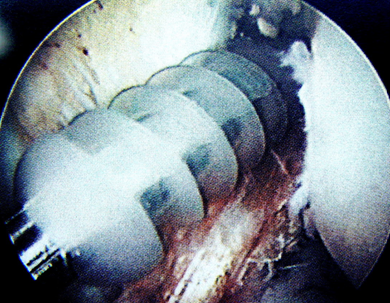

關(guān)節(jié)鏡下見(jiàn)重建的前交叉韌帶